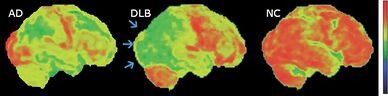

FDG-PET of brain surface, with the color red indicating areas of high metabolism. The occipital lobe in DLB (arrows) shows less activity than in AD.

While 74% of people with autopsy-confirmed DLB had deficits in planning and organization, they show up in only 45% of people with AD.[147] Visuospatial processing deficits are present in most individuals with DLB,[66] and they show up earlier and are more pronounced than in AD.[148] Hallucinations typically occur early in the course of DLB,[5] are less common in early AD, but usually occur later in AD.[85] AD pathology frequently co-occurs in DLB and is associated with more rapid decline; cerebrospinal fluid (CSF) testing may reveal an "Alzheimer's pattern" of higher tau and lower amyloid beta.[130]

PET or SPECT imaging can be used to detect reduced dopamine transporter uptake and distinguish AD from DLB.[57][149] Severe atrophy of the hippocampus is more typical of AD than DLB.[150] Before dementia develops (during the mild cognitive impairment phase), MRI scans show normal hippocampal volume. After dementia develops, MRI shows more atrophy among individuals with AD, and a slower reduction in volume over time among people with DLB than those with AD.[33] Compared to people with AD, FDG-PET brain scans in people with DLB often show a cingulate island sign.[33]